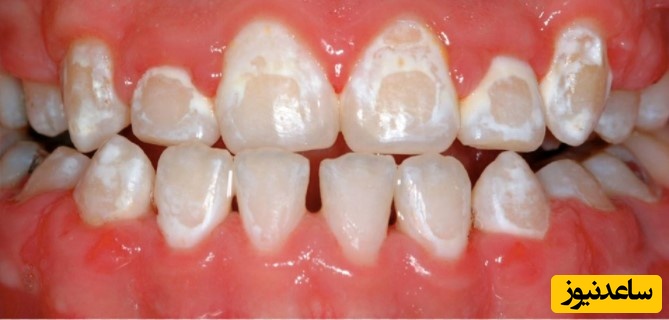

به گزارش سرویس سلامت ساعدنیوز، لکه های سفید دندان نشان دهنده اولین مرحله پوسیدگی و ایجاد کرم خوردگی دندان است. لکه های سفید نواحی هستند که دندان مواد معدنی خود را از دست داده است و مقاومت ندارد. زمانی این لکه های تشکیل می شود که دندان در معرض اسید حل شده و مواد معدنی آن جدا شده اند. حمله اسیدی به دندان باعث ایجاد هزاران سوراخ ریز در مینای دندان می شود. این سوراخ ها ظاهر سفید رنگ گچی دارند که آنها را به عنوان لکه های سفید می شناسیم.

لازم به ذکر است که لکه های سفید دندان با مسواک زدن و نخ دندان کشیدن درست، 100% قابل پیشگیری هستند. 10 تا 20% از کودکان در دوره ارتودنسی دچار لکه های سفید دندان می شوند.

علت ایجاد لکه های سفید در دندان ضعف در رعایت بهداشت دهان است. پاک کردن پلاک ها از سطح دندان اهمیت زیادی دارد چرا که باکتری های موجود در پلاک، اسید تولید می کنند و این اسید مینای دندان را حل کرده و از بین می برد. افرادی که براکت ارتودنسی دارند بیشتر در معرض این وضعیت قرار دارند اما در حالت عادی نیز در صورتی که به درستی دندان های خود را مرتباً مسواک نزنید این لکه های سفید ایجاد می شود.